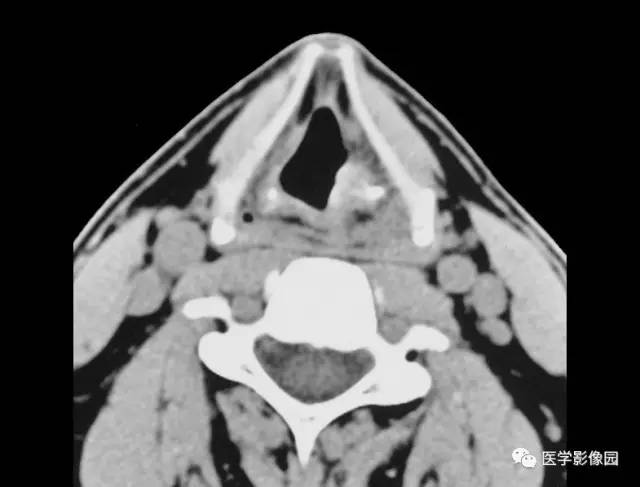

3.声带和室带可不规则增厚或形成软组织肿块(图3-5-10)。

4.病灶周围喉旁间隙多正常,常不向深部浸润,成人如有深部浸润应提示有恶变可能。

图3-5-10 喉乳头状瘤A.B.

CT平扫见左侧室带后部局限性软组织肿块,

并向喉腔突入(↑),喉旁间隙显示清晰